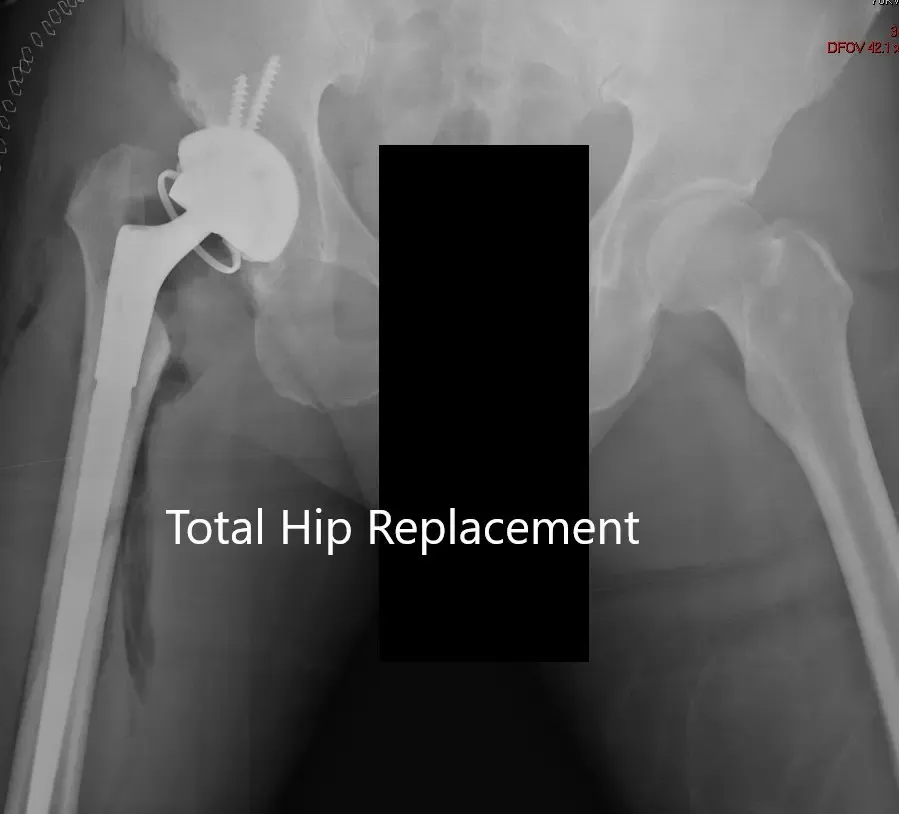

Postoperative X-ray showing AP view of the pelvis.

The recovery of the patient was unremarkable. He was started on aspirin 325mg BID for deep vein thrombosis prophylaxis. The pain was managed with medications. Hip precautions were explained to the patient. Weight-bearing was allowed as tolerated. Postoperatively there was no neurological deficit in bilateral lower extremities.